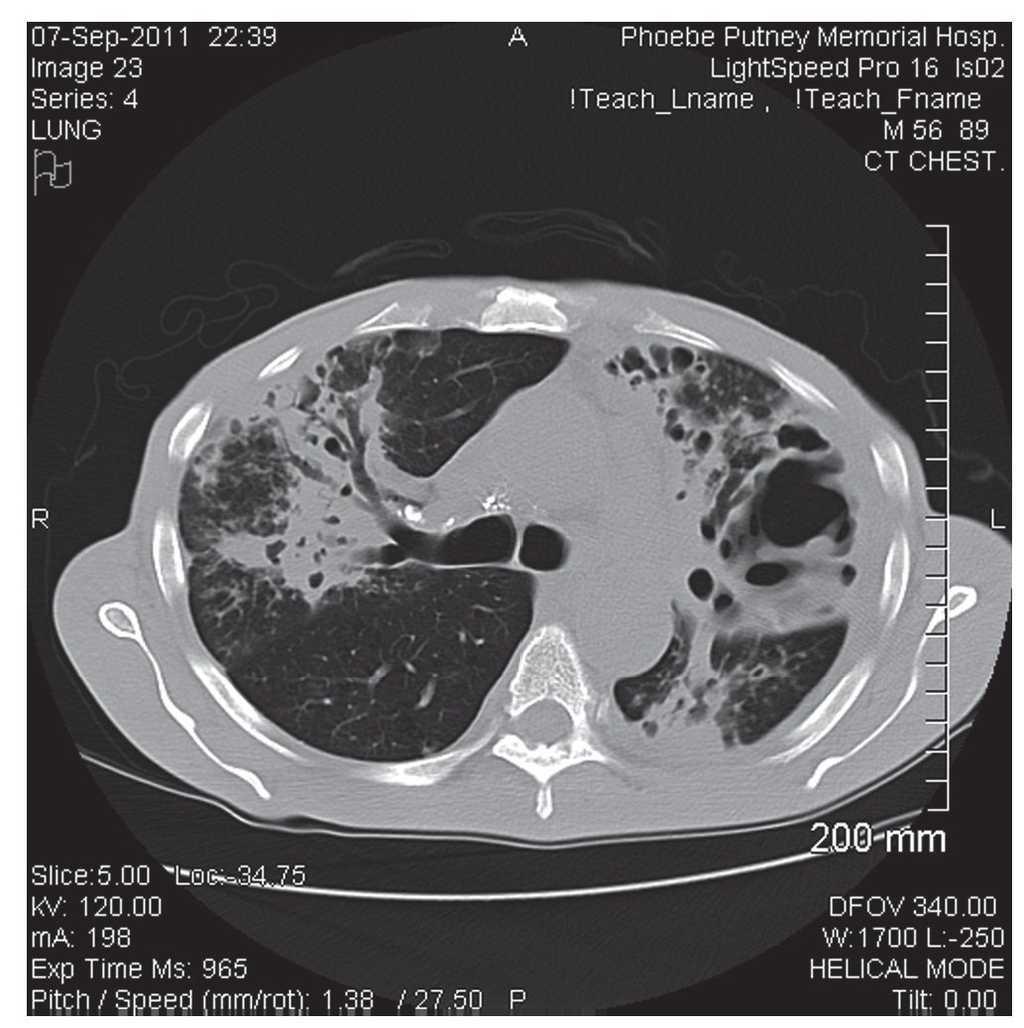

We conducted a descriptive, observational and retrospective review of clinical cases of suspected pulmonary TB (TB Class V as per the International Union Against Tuberculosis and Lung Disease) during a 2-year period (September 2011 to September 2013) in two large districts in southwest Georgia (U.S.) to identify the number of those infected with bacterial pathogens in the group of Actinomycetales. We were particularly interested in identifying those cases where Tsukamurella spp. or Rhodococcus spp. were isolated during the clinical workup of cases of presumed pulmonary TB. We defined cases according to their clinical presentation (fever, night sweats, productive cough for many weeks, malaise, weight loss, and hemoptysis) and chest radiograph or CT scan of the chest with findings compatible with pulmonary TB (cavitary lesions, endobronchial spread of pneumonia, or upper lobe pneumonias) (Fig. 1).

Figure 1 Large cavitary lesion involving the posterior and lateral segments of the left upper lobe extending into the lingula. There is also consolidation with air bronchograms at the right upper lobe.